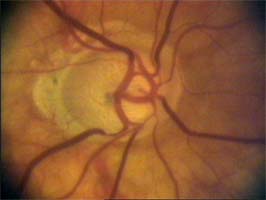

Na dolním pólu terče je patrný zálom vény, která zviditelňuje přítomnost i hloubku exkavace až k dolnímu okraji terče.

V nasálním horním kvadrantu terče vidíme obnažené cévy, které dříve probíhaly v lemu. Toto obnažení může být jedním z prvních příznaků glaukomové neuropathie.

(tenze 40-50 torr) Na obrázcích vidíme terče levého oka pacientky, u které se ani opakovanými operacemi nepodařilo snížit nitrooční tlak.

pacientka 2001

Kromě zvětšení a vertikálního protažení exkavace je zřetelné zúžení arterií, zatímco vény jsou zúženy jen méně zřetelně.